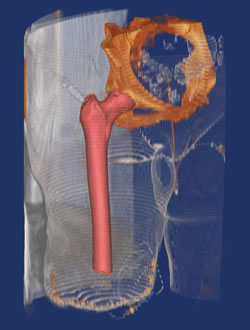

Figure 3. Modeling for custom implant.

Preoperative planning requires consideration of the local stump, including scars or burns as well as radiographic determination of the length and diameter of the prosthesis. A CT scan is helpful for determining the necessary implant size and limb length. Typically at least 12 to 15 cm of femoral shaft is needed for stable fixation.

3 D and Finite Element Modeling are done to provide for customization of the device for the individual bony parameters of the patient.

Surgeons are experts at making the most of conventional 2D image data to prepare for their surgeries. However, even the best planners can struggle with limited information that is available in 2D /images and with the inability to try out multiple approaches before entering the OR. Fortunately, 3D virtual surgical planning is available to remove many of the hurdles involved in determining the best plan and transferring it to reality.

Figure 7. Modeling from CT scans. |

Figure 8. Modeling with IM rod checking length, diameter and curvature. |